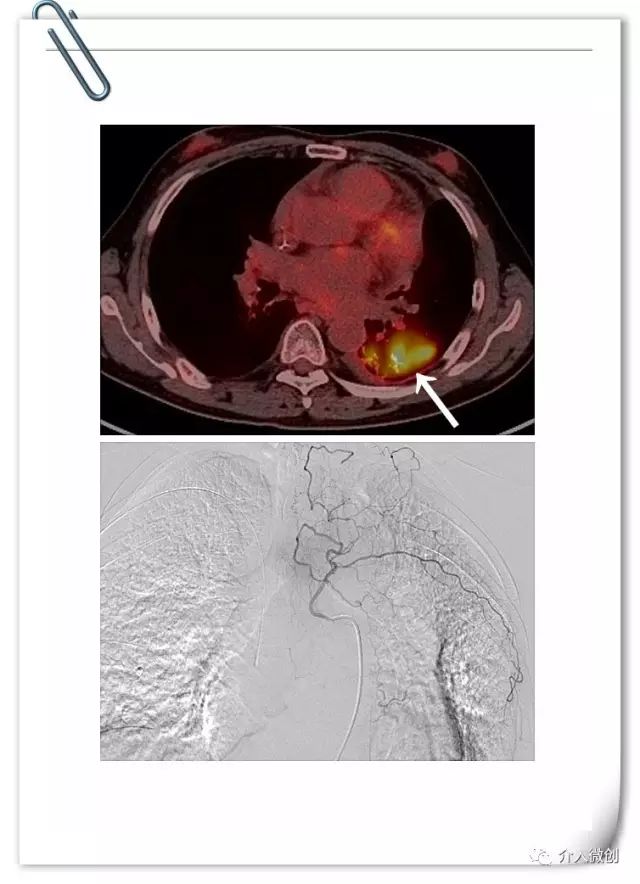

最终患者寻求介入微创治疗,术前PET-CT示左下肺高代谢病灶。DSA下行左支气管动脉化疗灌注术。考虑既往患者多程化疗后出现多次严重骨髓抑制,骨髓造血功能已严重受损,将其化疗剂量降至常规静脉化疗方案剂量的一半!

患者顺利完成2周期动脉灌注化疗,耐受性良好,无明显化疗毒副反应。术后1月后复查CT示左下肺病灶基本消失,术后随访3年余病情一直持续稳定,疗效评价完全缓解。